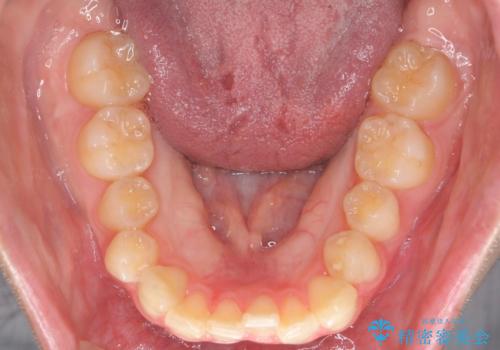

前歯のねじれをマウスピース矯正で治したい

- 前歯のねじれや がたつきを治したい、マウスピース矯正治療を希望され来院されました。

初診時程度のがたつきやねじれであれば、26枚以下のマウスピース矯正 モデレートプランで、比較的リーズナブルに矯正治療を受けていただくことができます。

実際の治療期間は約半年で仕上がりのような綺麗な歯並びを手に入れることができました。